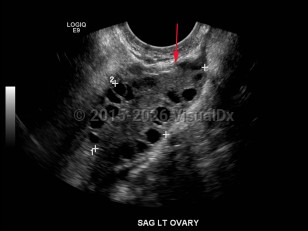

Although the exact etiology of the syndrome is unclear, women with PMOS have increased luteinizing hormone (LH) and low-to-normal follicle stimulating hormone (FSH). This is either a result of some inherent fault of hypothalamic-pituitary function, improper hypothalamic-pituitary-ovarian feedback mechanisms, or both. The increased LH stimulates an overproduction of androgens in the ovary; while some androgen will be converted to estrogen by aromatase, the overall hormonal milieu within the ovary is androgen dominant. This leads to an environment in which none of the smaller, immature ovarian follicles can arise as a mature dominant follicle. As such, the ovary takes on a polycystic appearance, with an overabundance of small follicles causing a cystic architecture on ultrasound.

Although the exact etiology of the syndrome is unclear, women with PMOS have increased luteinizing hormone (LH) and low-to-normal follicle stimulating hormone (FSH). This is either a result of some inherent fault of hypothalamic-pituitary function, improper hypothalamic-pituitary-ovarian feedback mechanisms, or both. The increased LH stimulates an overproduction of androgens in the ovary; while some androgen will be converted to estrogen by aromatase, the overall hormonal milieu within the ovary is androgen dominant. This leads to an environment in which none of the smaller, immature ovarian follicles can arise as a mature dominant follicle. As such, the ovary takes on a polycystic appearance, with an overabundance of small follicles causing a cystic architecture on ultrasound.